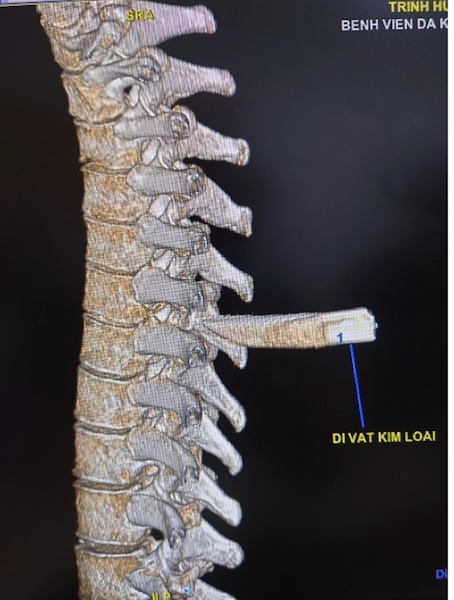

Nam thanh niên 30 tuổi bị dao đâm vào cột sống. Khiến phải mang cả mũi dao cắm sâu vào lưng đến bệnh viện cấp cứu. Các bác sĩ đã phải nhanh chóng lấy mũi dao ra khỏi người bệnh nhân.

Chiều 8/4, tin từ bệnh viện Đa khoa Trung ương Cần Thơ, các bác sĩ khoa Ngoại Thần kinh đã phẫu thuật cấp cứu lấy thành công mũi dao đâm vào cột sống nam bệnh nhân T.H.T.H, 30 tuổi, ngụ tỉnh Sóc Trăng.

Theo lời người thân bệnh nhân, H. bị đâm bằng dao sau lưng trái và nhanh chóng được đưa vào bệnh viện địa phương xử trí cấp cứu ban đầu. Sau đó, H. được chuyển đến bệnh viện Đa khoa Trung ương Cần Thơ lúc 10h40 ngày 7/4.

Tình trạng lúc nhập viện, bệnh nhân H. tỉnh, niêm hồng, than đau lưng, khó thở nhẹ với vết thương lưng thành ngực sau cạnh trái cột sống đoạn ngực 4-5 rỉ máu, còn dị vật, không tê yếu chi, dấu hiệu sinh tồn ổn định.

Các bác sĩ khoa Cấp cứu nhanh chóng xử trí cấp cứu và thực hiện các xét nghiệm, siêu âm, chụp Xquang tim phổi thẳng, chụp cắt lớp vi tính lồng ngực… Việc hội chẩn phẫu thuật được ê-kíp bác sĩ khẩn tiến hành và thống nhất phương án xử lý thám sát vết thương và lấy dị vật cấp cứu.

Sau 90 phút phẫu thuật, ê-kíp phẫu thuật gồm: Bs.CK2 Trần Văn Minh – Phó Trưởng, khoa Ngoại Thần kinh, Bs. Nguyễn Châu Thanh, Bs.CK1 Nguyễn Văn Vĩnh – Khoa Phẫu thuật – Gây mê hồi sức đã lấy thành công mũi dao dài 5x2cm ra ngoài.

Theo Bs.CK2 Trần Văn Minh, may mắn là trường hợp này mũi dao chưa gây vết thương tủy sống, nếu tổn thương tủy sống bệnh nhân sẽ có rối loạn cảm giác, rối loạn vận động, liệt tủy không hoàn toàn với các biến chứng dò dịch não tủy, nhiễm trùng, áp xe, viêm màng não tủy.

Nếu mũi dao đi sâu hơn nữa sẽ chạm gây thương tổn các tạng xung quanh, tùy theo vị trí tổn thương: Động mạch tủy sống, phổi màng phổi, động mạch chủ, động mạch cảnh, gan thận, ruột…

Bác sĩ khuyến cáo, với những trường hợp tương tự điều đặc biệt lưu ý là không được tùy tiện rút vật xuyên thấu ra khỏi vết thương tại hiện trường tai nạn hoặc ngay cả trong phòng cấp cứu, mà cần được đánh giá bằng các công cụ chẩn đoán hình ảnh như siêu âm, xquang, chụp cắt lớp vi tính trước để có thể lường được mức độ tổn thương và các nguy cơ tai biến có thể xảy ra khi rút vật xuyên thấu.